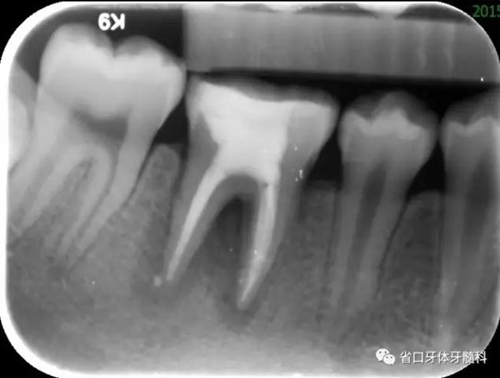

圖2 根管治療術(shù)后即刻X線片